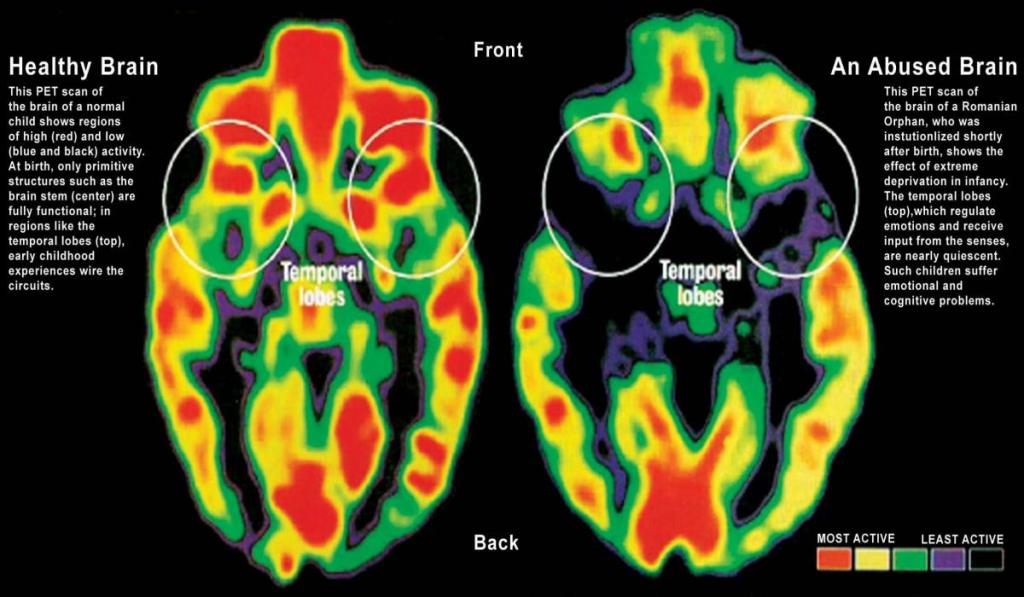

Brain scans show clearly that there are portions of the brain that do not develop and/or are not active when people are exposed to neglect and abuse.

Trauma impacts brain development by keeping a child trapped in the limbic system and governed by flight, fight and freeze. A child will spend most of their time in survival mode, which leaves fewer resources for social/emotional regulation and cognition.